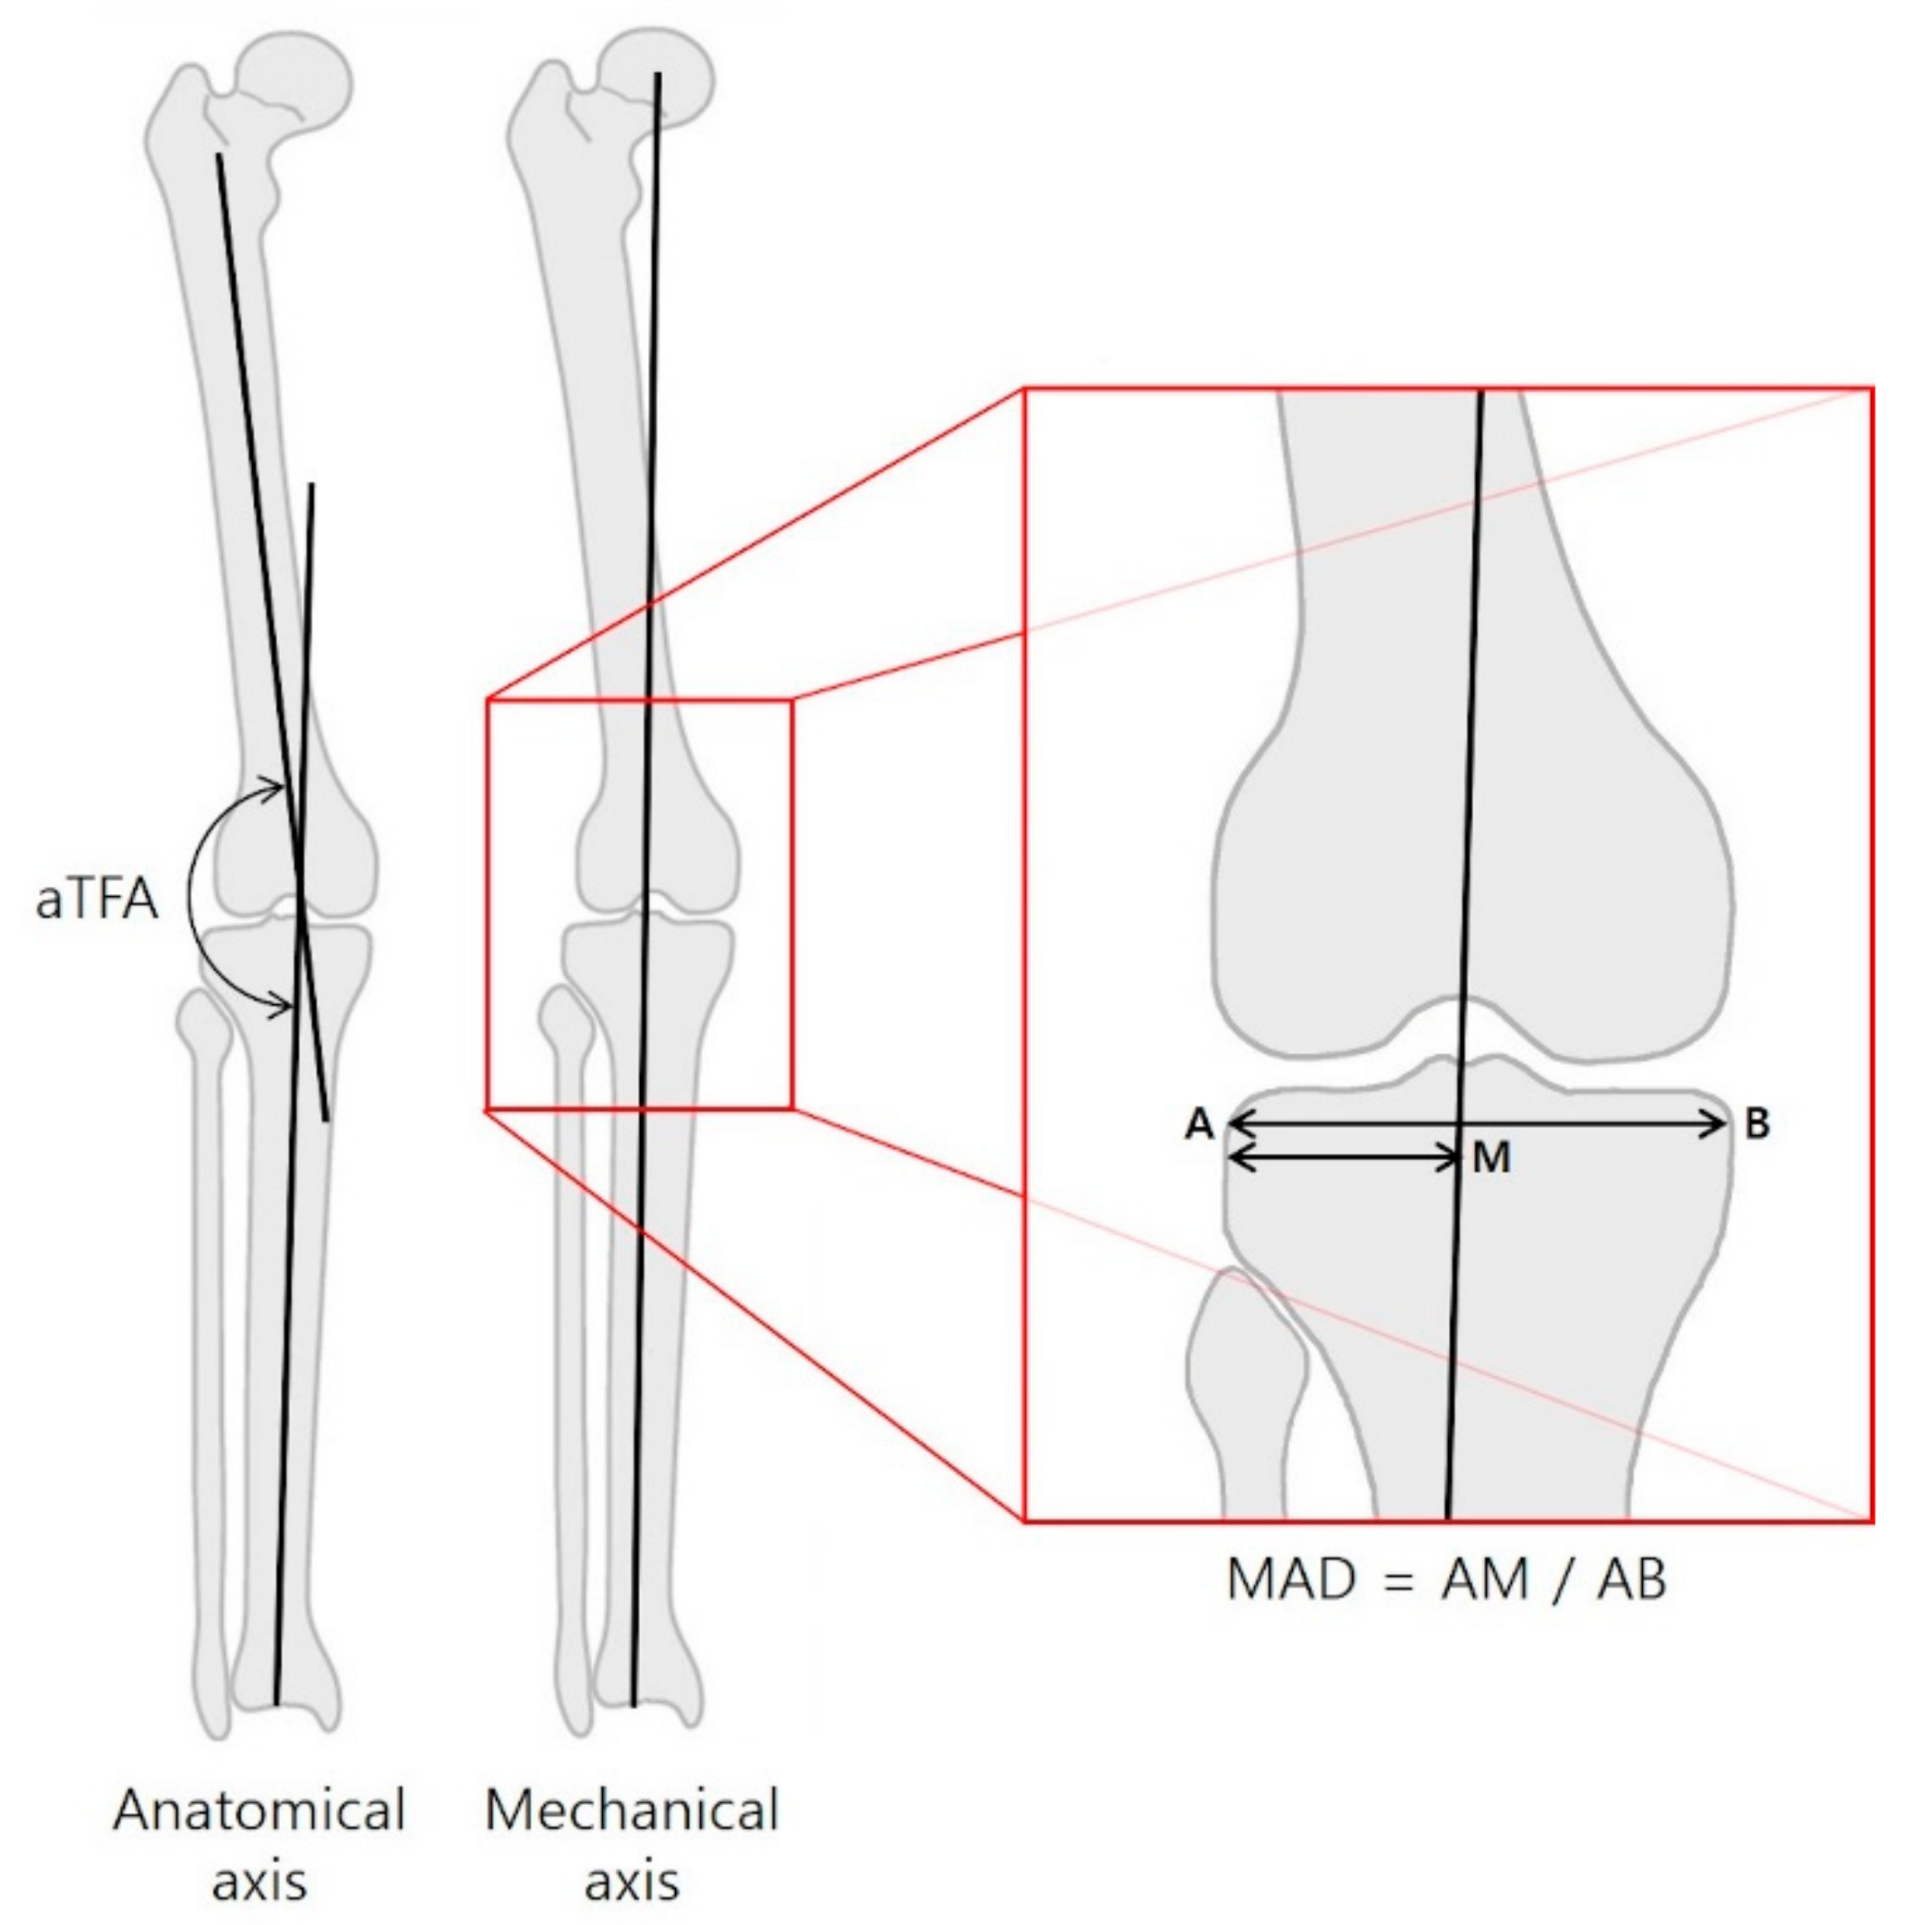

| MAD (ratio) | ||||

| Valgus | 0.32 ± 0.01 | 0.53 ± 0.01 | 0.21 ± 0.02 | <0.001 |

| Varus | 0.78 ± 0.02 | 0.47 ± 0.01 | −0.30 ± 0.03 | <0.001 |

| MAD (%/month) | Two Sample t-test | 4.27 ± 0.39 | 3.31 ± 0.4 | 0.137 |

| ANCOVA | 4.884 ± 0.324 | 3.094 ± 0.505 | 0.007 |

| Tip ratio AP | −3.765 (−9.865 to 2.336) | −0.152 | 0.231 | |||

| Tip ratio Lat | −2.767 (−7.460 to 1.926) | −0.145 | 0.252 | |||